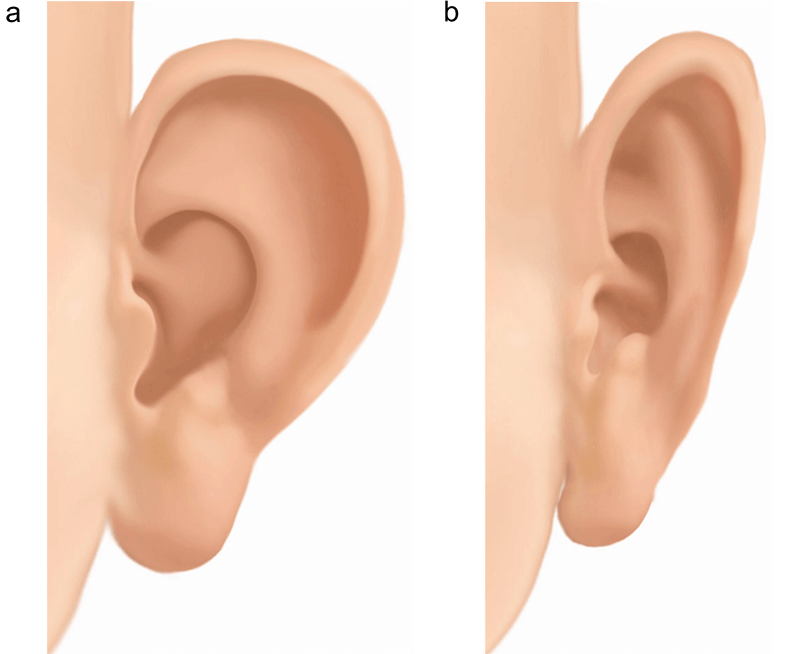

16. Otoplasty

16. Otoplasty